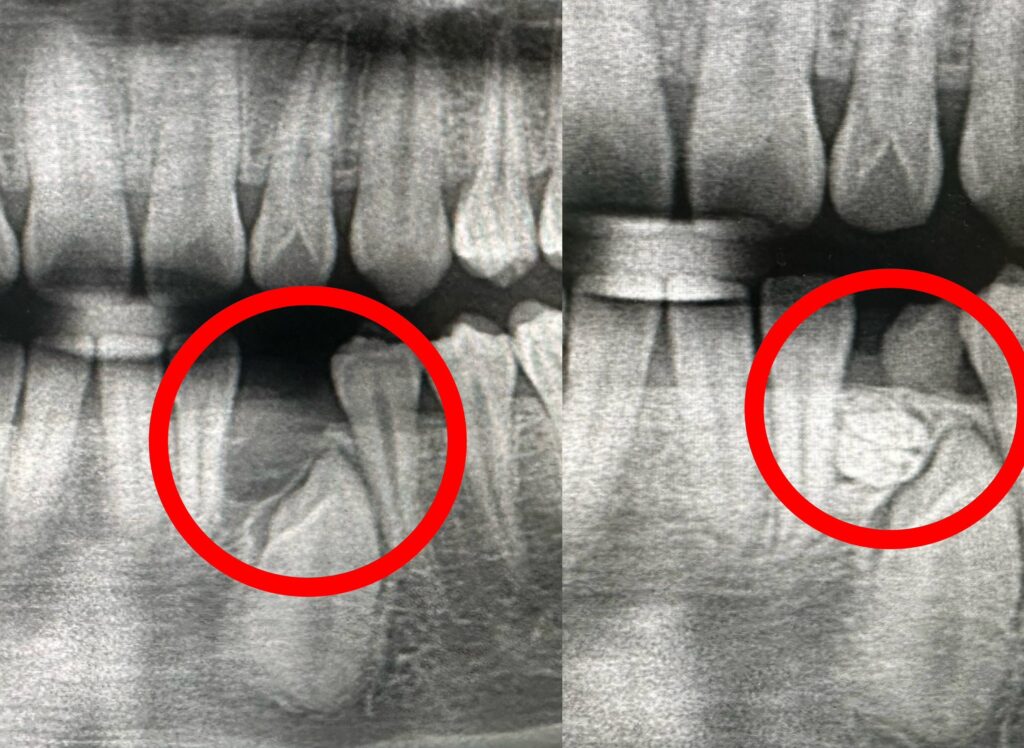

高中生原以為只是換牙較慢,沒想到透過X光檢查,竟在乳牙下方發現有約十顆牙齒組成。(記者孫義方攝)

透過X光檢查,竟在乳牙下方發現有約十顆牙齒組成的「齒瘤」。(記者孫義方攝)

朱晃照主任指出,齒瘤是口腔顎骨中最常見的良性齒源性腫瘤之一,但其實屬於牙齒發育異常形成的錯構瘤,內含牙釉質、牙本質與牙髓等組織,可能呈現為一顆顆迷你牙齒(混合性齒瘤),也可能是不規則鈣化團塊(複合性齒瘤),而本案例正是典型的多顆牙齒型態。